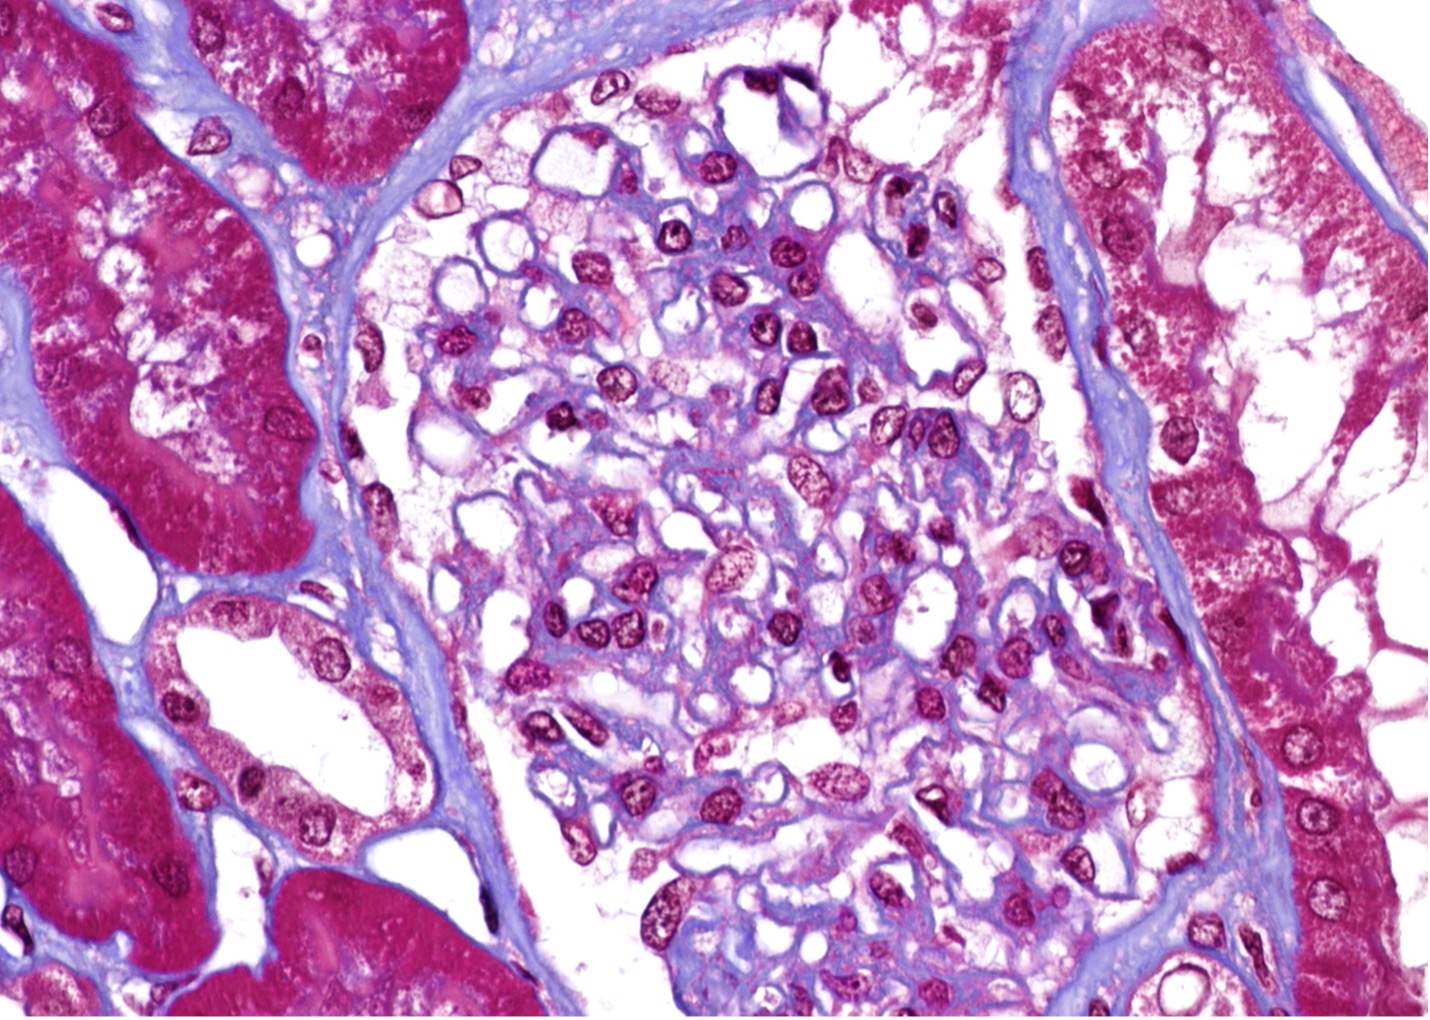

Figure 1 (Microscopic Photo, 400x) Diffusely and segmentally, podocytes have expanded cytoplasm with a marked foamy appearance (arrows, trichrome stain).

Kidney biopsy pathologic findings by light microscopy (LM) and electron microscopy (EM) are quite characteristic in Fabry disease. LM shows visceral glomerular epithelial cells (podocytes) and distal tubular epithelial cells with expanded cytoplasm and a marked foamy appearance (vacuolization), most prominent on the trichrome stain and seem as blue inclusions on toluidine blue stained plastic embedded LM of the EM specimen10. EM reveals podocytes that have prominent and expanded cytoplasm that contains numerous rounded electron-dense lipid inclusions (myelin figures, aka zebra bodies). Myelin figures or zebra bodies represent deposits of Gb3 primarily within enlarged secondary lysosomes as lamellated membrane structures11. These inclusions, composed of concentric layers with a periodicity of 3.5 to 5 nm and often an onion skin appearance, are considered a hallmark of glycolipid storage disorders12. These lipid inclusions may be seen in all glomerular cell types (most prominently podocytes), arteriolar smooth muscle cells, and tubular cells (mostly distal tubules) 11. Podocyte foot process effacement may range from focal to diffuse. Immunofluorescence staining does not typically contribute to the diagnosis but may be useful in excluding other coincident kidney disorders.